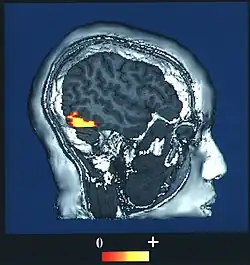

![]() Computer-enhanced fMRI scan of a person who has been asked to look at faces. The image shows increased blood flow in cerebral cortex that recognizes faces (FFA). | |

The fusiform face area (FFA, meaning spindle-shaped face area) is a part of the human visual system (while also activated in people blind from birth[1]) that is specialized for facial recognition.[2] It is located in the inferior temporal cortex (IT), in the fusiform gyrus (Brodmann area 37).